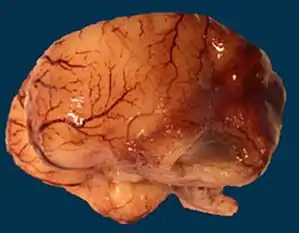

| Microlissencephaly in a 27 WG (week of gestation) foetus with TUBB2B mutation. Macroscopical view of the left hemisphere showing agyria, absent sylvian fissure and absent olfactory bulb. | |